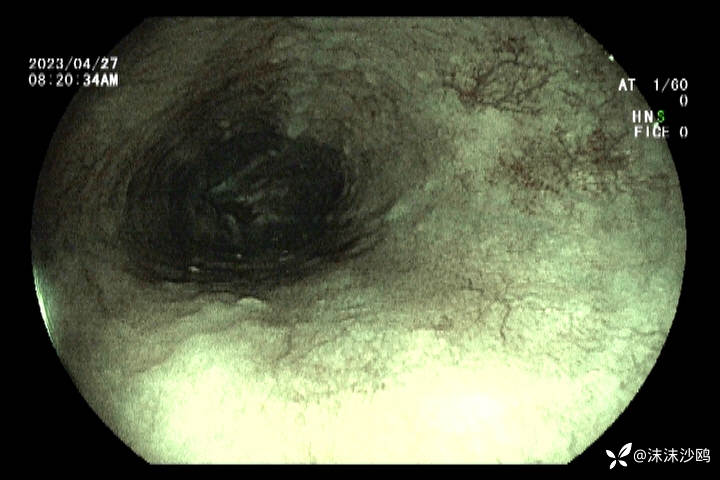

23年4月份

今天的,做了放大,但我们没有碘染色剂,所有没做碘染。

后三次都是我做的,因为今天对比了病灶,感觉变化不明显,没有取病检。